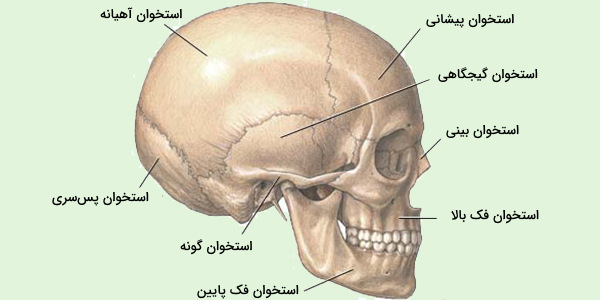

دانلود عکس اسکلت انسان دانلود عکس آناتومی بدن خانم از پشت و جلو دانلود عکس باکیفیت جمجمه انسان.

اسکلت جمجمه و گردن انسان ستون فقرات آناتومی اسکلت جمجمه و گردن انسان ستون فقرات آناتومی تصویر با کیفیت را از لینک زیر می توانید دانلود کنید. ۱ مطلب با کلمه ی کلیدی عکس اسکلت بدن انسان با کیفیت ثبت شده است گالری نسیم جدید ترین و با کیفیت ترین عکس های مناسبتی. عکس با کیفیت آناتومی اسکلت بدن انسان و درد و دیسک در قسمت مهره های ستون فقرات کمر ویژه استفاده در امور تبلیغاتی و تجاری طراحی کاتالوگ بروشور و تراکت با موضوع بیمارستان ها و کلینیک ها و درمانگاه ها و مطب ها پزشکان و.